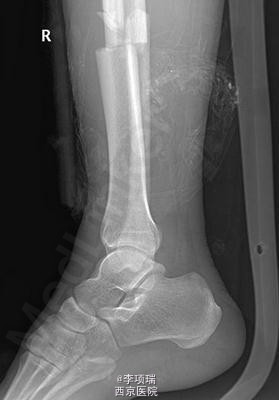

患者车祸外伤致右小腿肿痛、畸形约2小时。

查见右小腿轻度肿胀,无出血,胫前多处皮肤挫伤,淤紫,及骨擦感、异常活动。